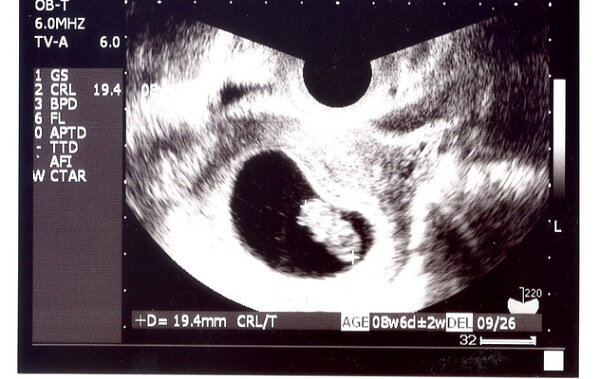

妊娠3ヶ月(8~11週)イチゴ1個くらいの重さ

3ヶ月後半になると頭殿長は約47㎜、身長は約75㎜ほどになり、体重は約20gになります。頭と胴体、手足の区別がはっきりとしてきます。

だいぶ赤ちゃんらしい形になりますが、脳が他の器官より早く成長するので、頭は体全体の半分を占めています。小さな小さな顔には目や鼻がはっきりみえてきて、乳歯の芽もできてきます。